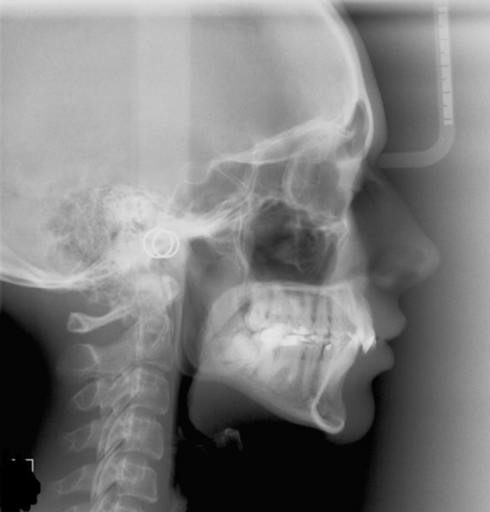

I am 26 yr old female and i have finally gathered the money to get my braces done. Over the years i have been told that my lower jaw is "pushed back" and it could cause problems when am older. The last orthodontist i went to, mentioned that i have an overjet but he is not sure if thats whether my lowerjaw is pushed back or because my upper jaw is forward so he told me to get my x-rays done. He gave me three options (he has not seen the X-rays yet): Option 1: Have a surgery but i cannot afford to do so. Option 2: Remove two teeth from my upper jaw which will help push the upper jaw back a bit so it will meet with my lower jaw. Option 3: Do not remove any teeth, teeth wil be straightened but there will be a small gab between my upper and lower jaw. Option 2 Scares me. I have heard my whole life that my lower jaw is pushed back(especially when i talk/smile) and the idea of forcing my upper jaw back aswell seems unsetteling. I like option 3 , however, is it really okay that my uper and lower teeth will have a gab between them? will that cause any problems in the future? p.s. I am getting Lingual braces.

First you need to set your goals and expectations. What do you like about your smile and what would you change. If you just want your teeth straight, then overjet and molar relationship doesn't matter. If you don't want to remove teeth, dont. Your orthodontist is giving you options so you can decide what's important and what's not. Having a small amount of overjet will not create problems for you in the future. You need to be happy with your smile and confident that you have made the best choice to meet your treatment goals. The best option is whatever you feel most comfortable with.